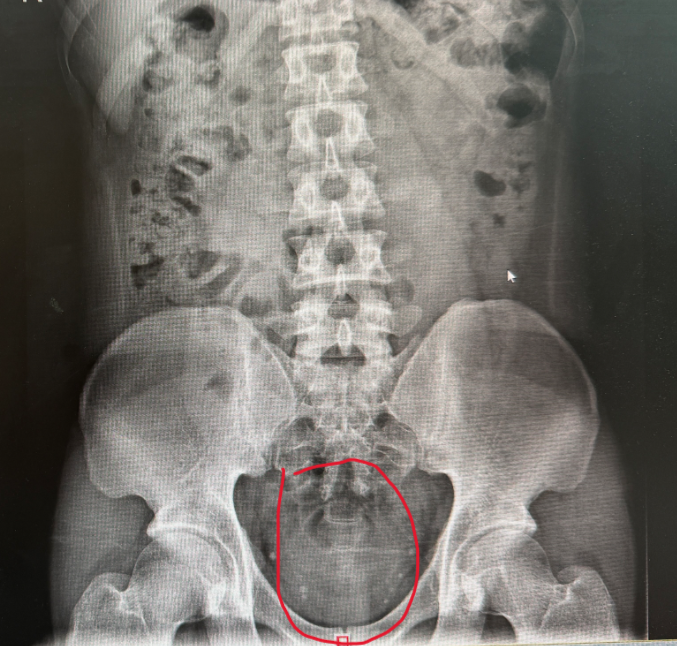

急诊科医生在指诊时发现,确有一明显异物藏于刚哥肛门内,但由于异物已被肛门“吞没”,肉眼无法观察到其形状和大小。为方便后续治疗,急诊医生立马给刚哥安排上了DR(X光)。

但没想到,X光图像却无法清晰显示异物的形状和大小,只能隐约看到稍高密度影。一问刚哥才知道,原来异物是透明硅胶材质,这才导致X光无法清晰照射出异物形状。

X光可见直肠稍高密度影